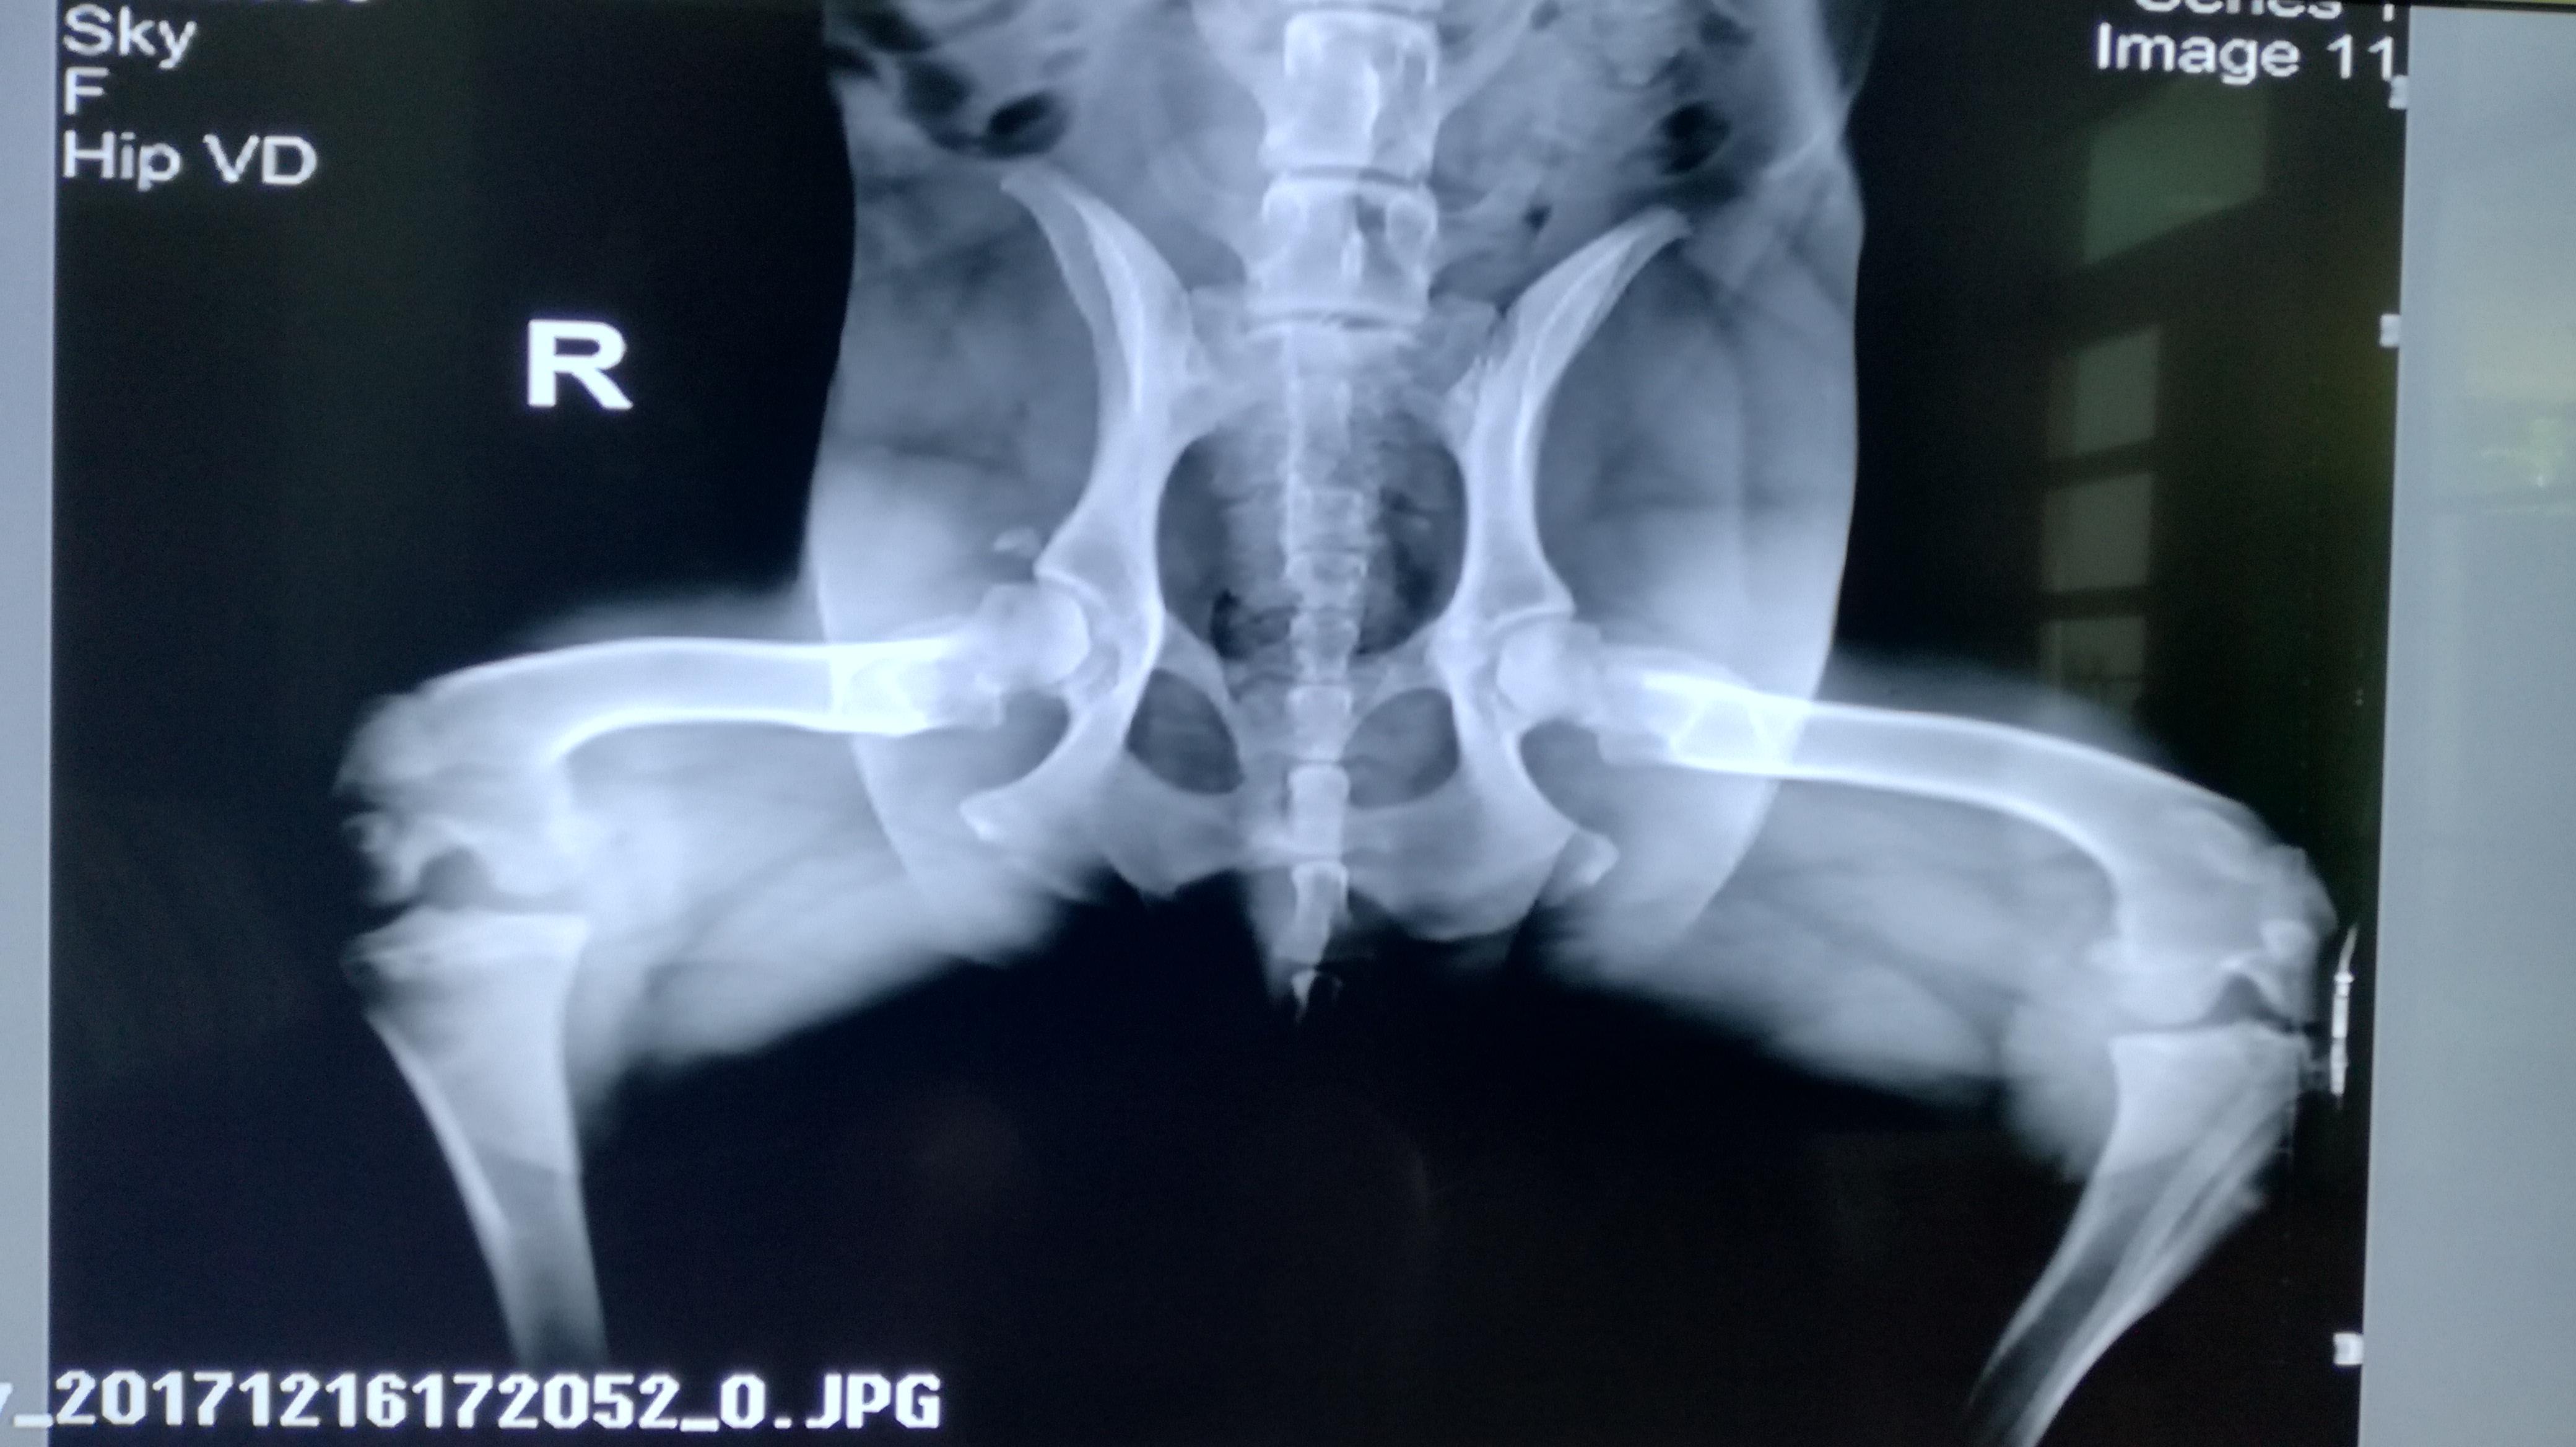

My 8-yr old golden retriever limped (right hind leg) recently. Took X-ray. There is a lose bone fragment floating around. Prescribed Rimadyl 75mg for 5 days. It improved but then he gets limp easily. What has happened? What can we do? Thanks a lot

Generally that little piece of bone will eventually scar down to the joint capsule and will not cause much of a problem. If it becomes a chronic source of lameness, it can likely be arthroscopically removed. The thought is that maybe there was some arthritis forming and a small piece broke off. It could also be the result of trauma or a developmental condition causing a flap of unhealthy bone to form of the femoral head that eventually broke off. Please post again if you have any further questions.